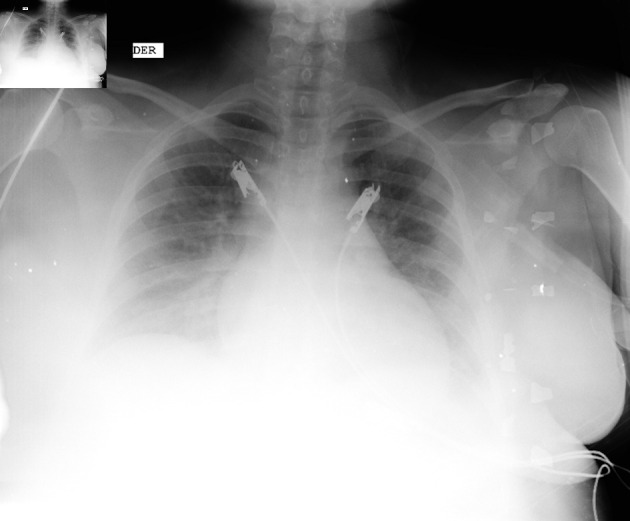

围产期心肌病(PPCM)是孕产妇健康的重大挑战,其特点是在妊娠晚期或产后早期出现射血分数降低的心力衰竭。尽管人们对 PPCM 的认识有所进步,但它仍然威胁着产妇的生命,并导致大量产妇发病和死亡。本文回顾了与 PPCM 相关的流行病学、病因学、诊断难题、管理策略和结果。本文报告了一名 29 岁女性 PPCM 患者的病例,强调了早期识别和针对性治疗的重要性。患者发病时症状不典型,包括排尿困难、腰痛、持续发热和口服不耐受。尽管进行了积极的医疗干预,但患者还是在入院后 48 小时内因心肺骤停而不幸去世。本病例凸显了诊断和管理 PPCM 所面临的挑战,尤其是在出现非特异性症状时,并强调迫切需要改进诊断标准和治疗干预措施,以减轻患者的不良后果。

Peripartum cardiomyopathy (PPCM) poses a significant challenge in maternal health, characterized by heart failure with reduced ejection fraction during late pregnancy or early postpartum. Despite advances in understanding PPCM, it remains life-threatening with substantial maternal morbidity and mortality. This article reviews the epidemiology, etiology, diagnostic challenges, management strategies, and outcomes associated with PPCM. A case report of a 29-year-old woman with PPCM is presented, emphasizing the importance of early recognition and tailored management. The patient's presentation was marked by atypical symptoms, including dysuria, lumbar pain, persistent fever, and oral intake intolerance. Despite aggressive medical intervention, the patient experienced a tragic outcome, succumbing to cardiopulmonary arrest within 48 h of admission. This case underscores the challenges in diagnosing and managing PPCM, particularly when presenting with nonspecific symptoms and emphasizes the urgent need for improved diagnostic criteria and therapeutic interventions to mitigate adverse outcomes in affected individuals.